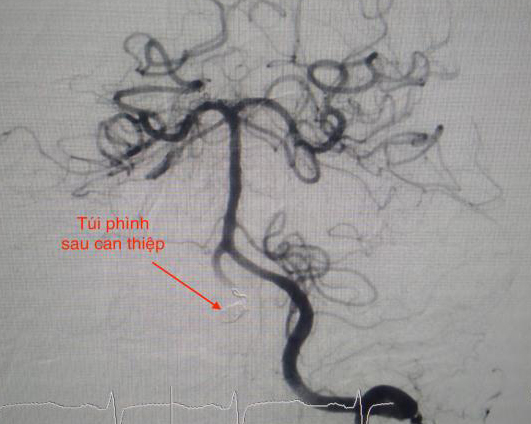

Và sau khi can thiệp thành công.

Ê kíp do BS Trịnh Thành Tín, BSCK1 Trần Công Khánh tiến hành can thiệp sử dụng 3 coil làm bít túi phình động mạch đốt sống.

Sau gần 2 giờ can thiệp, các BS làm bít hoàn toàn túi phình mạch não, tái thông dòng máu trở lại bình thường.

Hình ảnh sọ não sau khi can thiệp thành công.